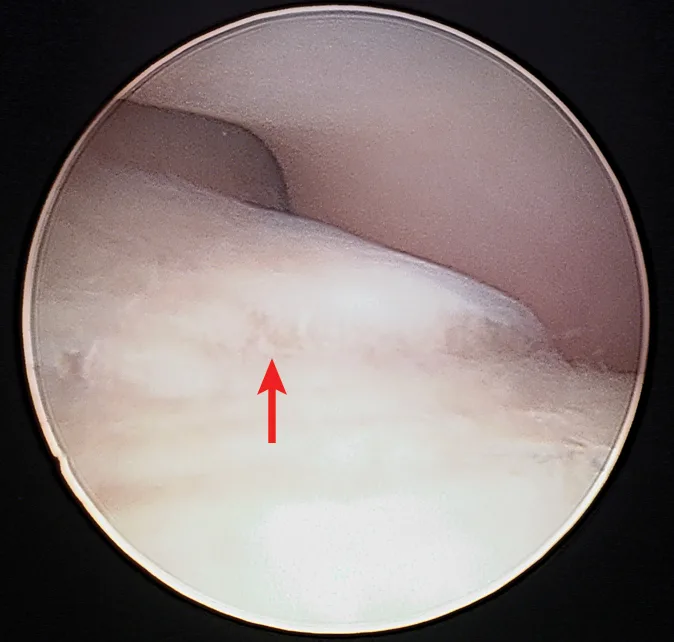

Both elbows were prepared for surgery. Maggie was premedicated with hydromorphone (0.1 mg/kg IM) and dexmedetomidine (3 μg/kg IM), and anesthesia was induced with propofol (4 mg/kg IV) and ketamine (1 mg/kg IV). A traditional brachial plexus block was performed on both thoracic limbs using a nerve locator and 0.5% bupivacaine (2 mg/kg). Bilateral elbow arthroscopy was performed to remove the suspected TFMCP in the right elbow and examine the left elbow for subclinical disease. The right elbow was found to have minimal signs of osteoarthritis. Fibrillation, which is characterized by splitting of the superficial layers of cartilage (modified Outerbridge system, grade 2), was the only observed cartilage abnormality and was localized to the region of the medial coronoid process. A large osteochondral fragment arising from the medial coronoid process was identified in the right elbow and removed (Figure 3), and an abrasion arthroplasty of underlying subchondral bone was performed using a mechanical shaver. Elbow incongruity was not appreciated on full arthroscopic examination. The left elbow appeared arthroscopically normal, with no cartilage abnormalities or signs of osteoarthritis. No additional abnormalities were observed.

Arthroscopic image of the right elbow. A large osteochondral fragment is arising from the medial coronoid process (arrow), and cartilage fibrillation is present.